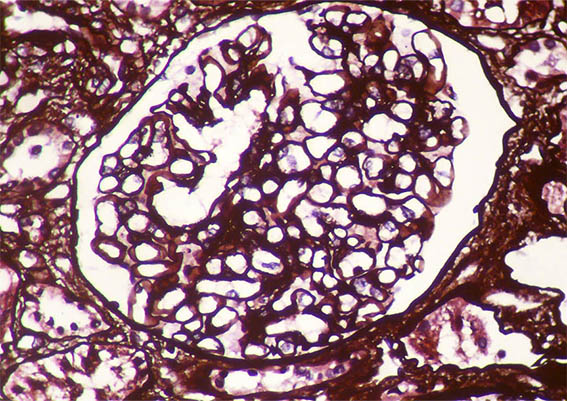

Figure 5. Methenamine-silver stain, X400. Normal capillary walls.

Figure 6. Methenamine-silver stain, X400.